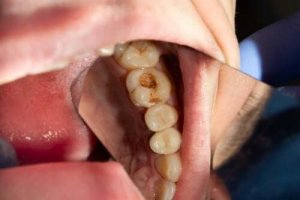

Hål börjar som vita fläckar med kritaktig textur på tänderna på grund av att emaljen förtunnas och försvagas. Om mineralerna fortsätter att förloras så kan tillståndet förvärras, varpå ett mörkt, gulaktigt hål visar sig.